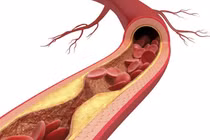

Từ ca bệnh điển hình này, bác sĩ Hải nhấn mạnh, khi bệnh nhân có các triệu chứng của tai biến mạch não như: Yếu hoặc liệt tay chân, mất ý thức, méo miệng, liệt nửa người, nhìn mờ... hoặc đã được chẩn đoán tai biến mạch máu não kết hợp với tiền sử có yếu tố nguy cơ tim mạch nên khám định kỳ và siêu âm Doppler động mạch cảnh.

Đây là phương pháp sàng lọc không xâm lấn nhằm phát hiện và đánh giá chính xác mức độ hẹp hoặc tắc nghẽn mạch máu não, từ đó đưa ra phương án điều trị, can thiệp kịp thời.